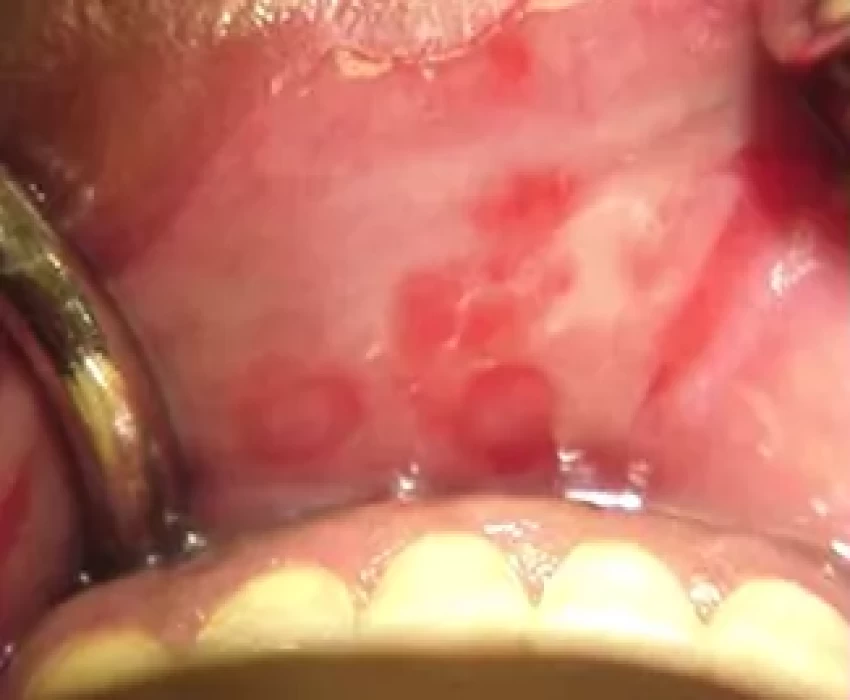

Certain OPMDs, such as oral submucous fibrosis, are encountered particularly with specific lifestyle habits. The main objective is secondary prevention by early detection of PMDs when they can be treated most effectively. PMDs are often undiagnosed due to lack of public awareness and due to lack of knowledge among medical professionals. Clinical appearance and diagnosis of a lesion is not adequate to determine its premalignant nature as not all white lesions turn malignant. Diagnostic biopsy and histopathological examination should be considered for any mucosal lesion that persists for more than 14 days after obvious irritants have been removed. Prognosis and patient survival is directly related to stage and grade of cancer at initial diagnosis. He has a keen interest in the management of Potentially Malignant Disorder